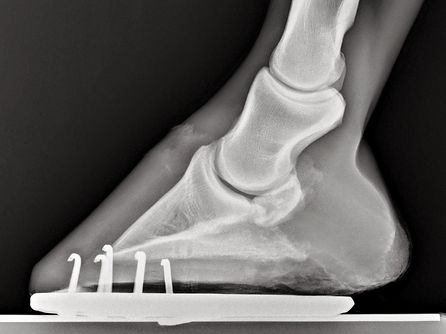

LM projekce posuzuje tvar, polohu a kvalitu kopytní, střelkové a korunkové kosti.

Obr. č. 1: Dobře LM zobrazená střelková kost u relativně mladého koně, protože na ní nejsou patrné známky reakce na zátěž, pěkné kortikomedulární rozhraní,(rozhraní mezi kostěnnou ploténkou ohýbačové plochy a dřeňovou dutinou) neprotažená facies flexoria (ohýbačová plocha) ani distálním ani proximálním směrem.